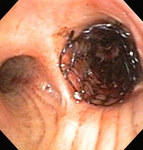

Бронхоскопическая терапия для обструкции нижних дыхательных путей правого главного бронха: размещение стента

Из коллекций Хосе Фернандо Сантакруза, дипломированного врача, члена Американской коллегии специалистов в области торакальной медицины, DAABIP, и Эрика Фолка, дипломированного врача, магистра наук; используется с разрешения